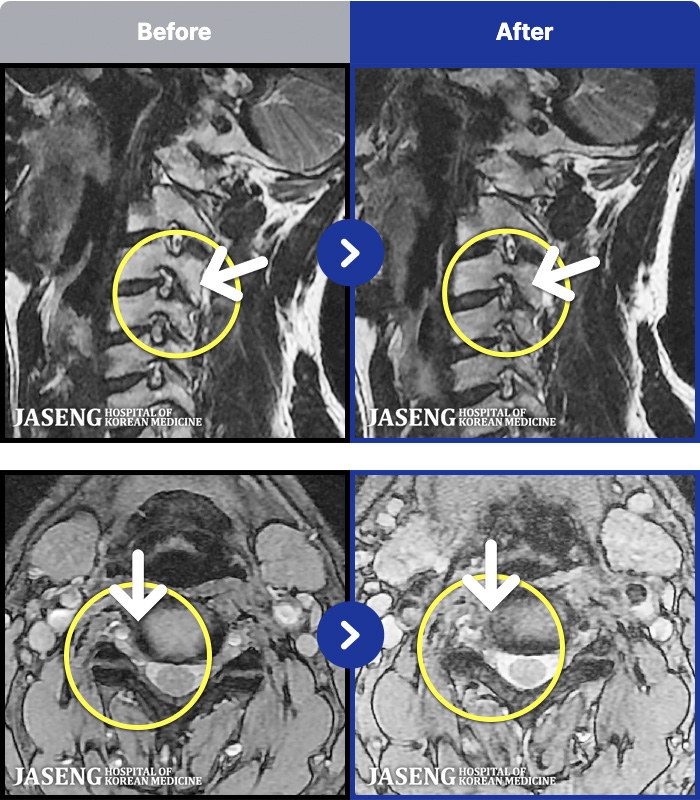

MRI ġ

1,240 MRI ũ ʸ Ȯϼ.